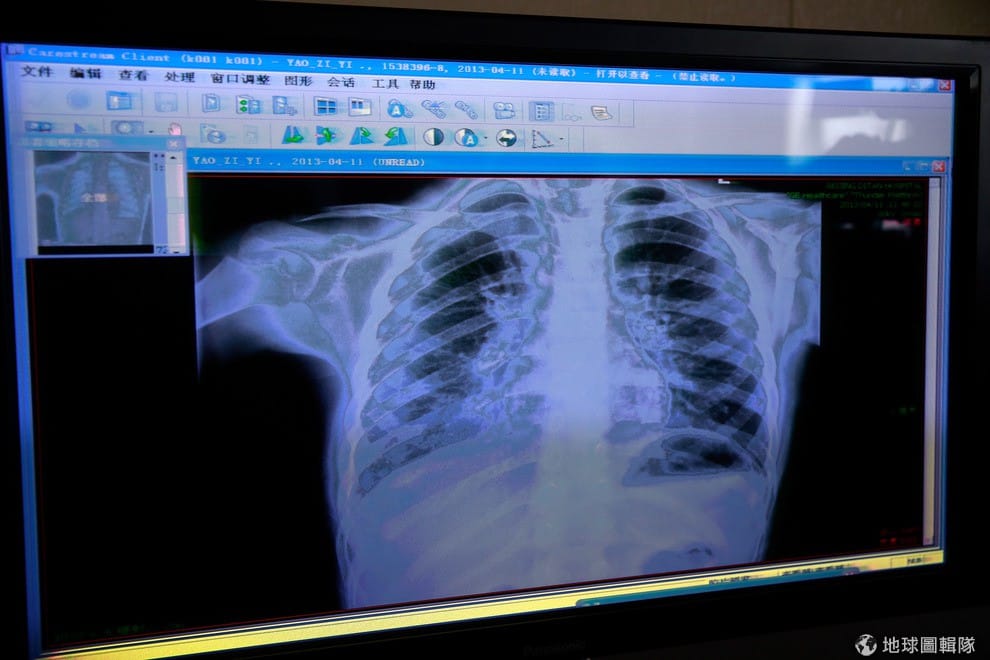

中國境內的禽流感疫情持續擴散,截至目前已有60明確診病例,其中已有13人不幸因病身亡。

《新華網》15號報導,中國境內感染H7N9的病患人數持續增加,光是在上周末就增加了11名確診病例,病患主要來自上海、江蘇、浙江、以及河南地區,目前確定感染H7N9病毒人數累計達到60人,其中已經有13位病患不敵病魔死亡。